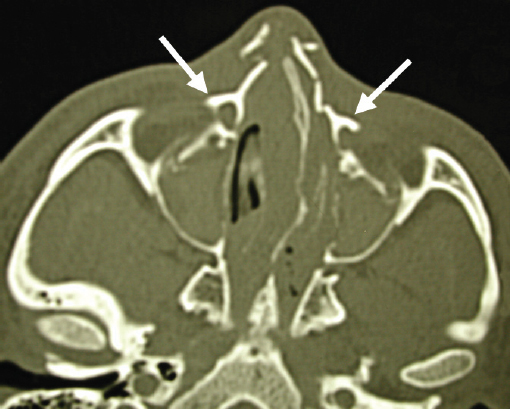

Historically, plain sinus X-rays were used to evaluate facial fractures. Thin cut (1–1.5 mm) axial computed tomography (CT) scans are now the gold standard for diagnosis of frontal sinus fractures. These images are readily reformatted into coronal, sagittal, and threedimensional (3D) reconstructions to improve the diagnostic accuracy. Axial cuts provide excellent information about the anterior and posterior table as well as pneumocephalus ( Fig. 63.5 ). Coronal reconstructions demonstrate the frontal sinus floor, orbital roof, and frontal recess ( Fig. 63.6 ). Sagittal views can assist with evaluation of frontal recess and skull base injuries ( Fig. 63.7 ). Threedimensional reconstructions can be very helpful in delineating the location of bone fragments and reducing the need for excessive dissection intraoperatively ( Fig. 63.8 ). Access to the PACS ( p icture a rchiving and c ommunication s ystem) or some type of presurgical planning software allows the surgeon to manipulate the reconstructions in space, gaining a greater understanding of depth and spatial relationships of the injury ( Video 63.1).

Injuries to the nasoorbitoethmoid complex can be difficult to diagnose, as they may be masked by facial edema. A complete head and neck examination should be performed including the brain, cervical spine, orbits, and presence of CSF leak. Both neurosurgery and ophthalmology consultations may be required. A high degree of suspicion must be maintained because failure to identify these injuries often results in deformities that are extremely difficult to repair secondarily. Physical findings suggestive of a nasoorbitoethmoid fracture include: (1) widening of the intercanthal distance greater than 30–35 mm; (2) blunting of the medial canthus and narrowing of the palpebral fissure width ( Fig. 63.52 ); (3) widening of the nasal dorsum; and (4) rotation, deprojection, and shortening of the nose. The integrity of the medial canthal tendon should be evaluated by carefully applying lateral tension to each lid. Normally, there will be a defined end point to the maneuver, without palpable motion at the canthal insertion ( Fig. 63.53 ). A periosteal elevator can also be inserted through the nose to apply lateral pressure in the same area. A lax medial canthal tendon, or medial orbital wall motion, is consistent with a nasoorbitoethmoid complex fracture. Telecanthus, enophthalmos, pupillary response, and extraocular muscle mobility should be assessed and documented. The degree of nasal or midface retrusion should be assessed. The surgeon should palpate the nasal dorsum at the nasion, rhinion, and tip ( Fig. 63.54 ). If there is significant lack of support along the entire nasal dorsum, an onlay calvarial bone graft will be required. Finally, thin cut (1–1.5 mm) CT scan with coronal, sagittal, and 3D reconstructions plays an important role in defining the pattern and extent of injury. The surgeon must assess the cribriform plate, frontal recess/sinus involvement, orbital integrity, degree of nasoorbitoethmoid complex comminution, and associated facial fractures. Characteristic radiologic findings include: (1) disruption and widening of the nasal dorsum in the coronal plane; (2) a “Y-sign,” occurring when the frontal process of the maxilla/lacrimal bone fractures at the insertion of the canthal ligament, resulting in a Y-shaped bone fragment ( Fig. 63.55 ); (3) depression of the nasal root; and (4) disruption of the frontal recess.